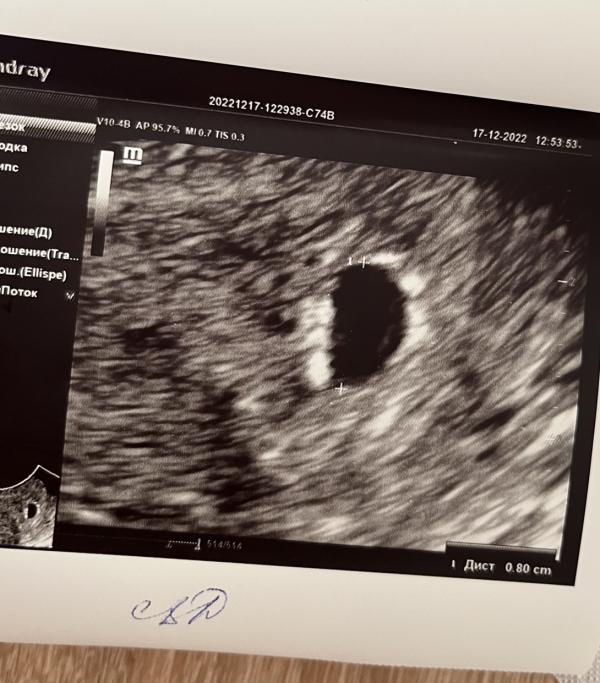

Беременность есть, 3 недели. Но есть маленькая угроза🥺 Гематома.

Сказали должна рассосаться эта гематома после приема утрожестана и на повторное узи через 3-5 недель. Я не понимаю почему приложение показывает такой большой срок и эмбриона если по факту там только 8мм.

У меня срок поставили 4-5 недель в ровно 5 недель по Мемячным когда я пришла. ПЯ было 4,7 эмбрион 1,2 мм